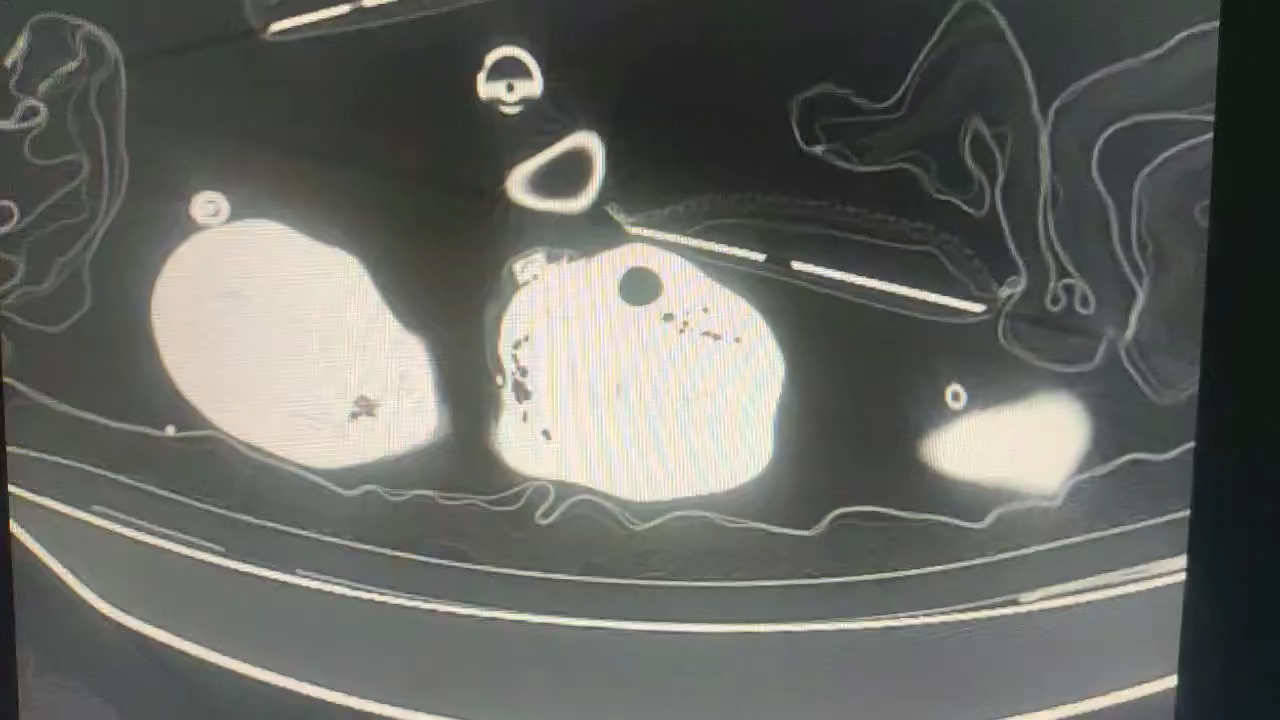

血生化及炎症指标较前有所改善,复查CT:

最新CT提示肺部感染情况较前明显加重。

患者通过系统抗感染治疗血检结果较前明显改善,但是动态影像学检查却有加重趋势,不尽如意,患者自主呼吸尚平稳,间断无创辅助呼吸。讨论问题:临床血生化炎症指标与影像学结果不是十分平行的话,继续维持当前治疗方案还是调整方案?